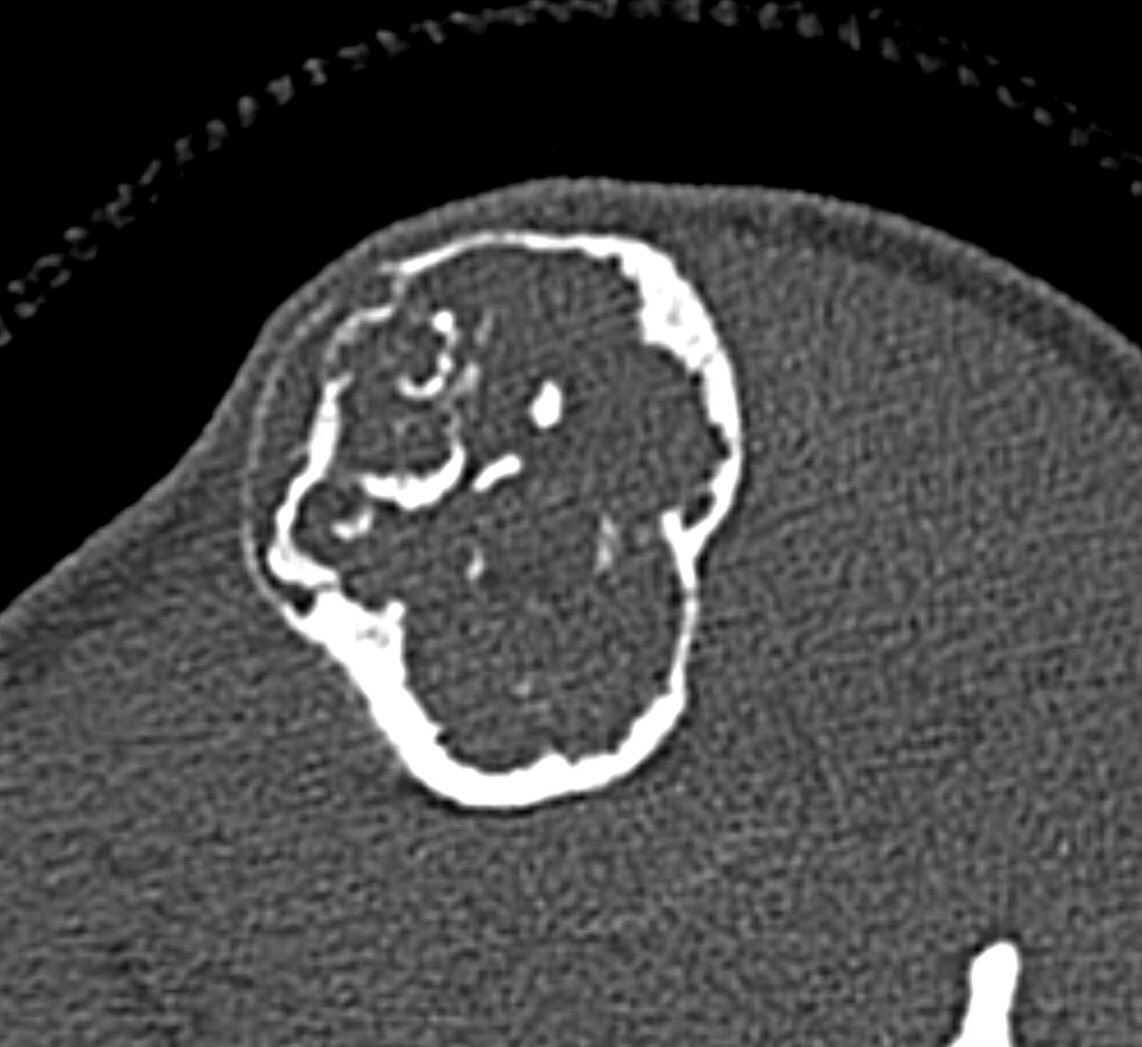

X ray of the tibia

Here a case of lower extremity pain

A single destructive lesion or multifocal tumour,may be identified, affecting cortex and often extending to the medulla,most commonly in the mid-tibial shaft.The lesion is typically eccentric and may cause mild bone expansion,endosteal scalloping and eventually destroy the cortex

AD typically appears multilocular and trabeculated, with intervening and surrounding sclerosis. A distinct periosteal reaction is unusual. An extra-osseous mass and pathological fracture may be seen